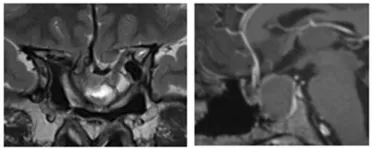

8年逃不过复发“魔咒”,突发中风、继发空碟鞍综合征

图2:术前MRI显示二次手术后肿瘤残余、患者出现继发性空蝶鞍综合征的影像学特征

继发性空蝶鞍综合征是个问题……

医生说,除了肿瘤残余的问题,继发性空蝶鞍综合征也是一个相对复杂的疾病,其引起的垂体功能低下和视力下降是长期慢性的过程。在此过程中,垂体、视交叉受压变细、变薄、向后下方移位;供血的细小血管也会牵拉延长变细。关于空蝶鞍综合征的手术技巧报道较少,现有文献报道中,空蝶鞍综合征术后发生并发症机率较高。由于视神经通路和交叉被肿瘤拉伸的时间较长,并伴有粘连,可能导致病变切除后裂开的鞍膈肌和交叉向下移位。因此,由于术后瘢痕组织的发育而引起的回缩可逐渐增加牵拉的程度,这也解释了术后数月或数年内经常发生的延迟视力损害。

开颅手术、经鼻手术、硬膜外复位、硬膜下复位,治疗方式繁多。如复位速度过快,程度过多,可能出现视交叉快速移位,小血管撕裂,造成视力快速下降等不可逆的严重并发症(文献报道可出现颅内出血、视力快速下降)。